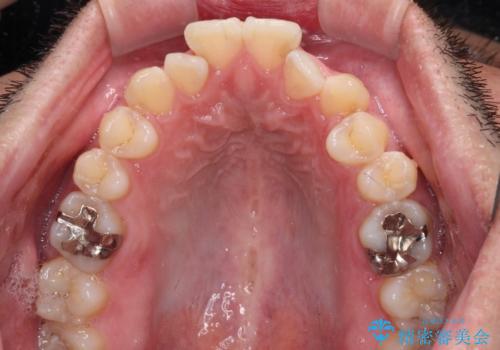

開咬とデコボコを整える インビザライン矯正治療

- 前歯の開咬と叢生を気にして来院された患者様です。

開咬の治療は、前歯を閉じるように動かすとともに、上下臼歯を圧下(骨内にめり込ませる)させることで進めて行きます。

インビザラインは臼歯の圧下を効果的に行えるため、インビザラインを用いて矯正治療を行うこととしました。また、アンカースクリューを用いて、口元の突出感の改善を図りました。